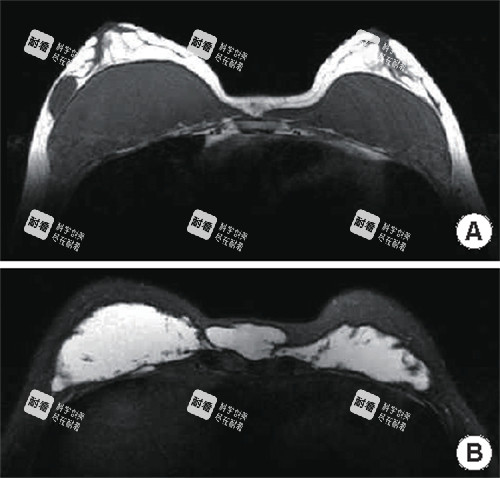

很多人以为奥美定取出就是“挖出来就行”,其实远远没那么简单。奥美定是一种水凝胶类物质,注射后会随着时间慢慢游走、分散,甚至包裹在组织里。如果用传统方式粗暴刮除,不仅容易残留,还可能伤到血管神经,反而加重术后反应。

现在正规医院普遍采用的是“全息六维层离清奥术”,配合3D内窥镜技术,就像给身体装了个高清导航仪——医生能清晰看到每一处奥美定的分布位置,逐层分离、温和稀释,避开重要组织,实现“干净又可靠”的取出。这种技术特别适合那些注射时间久、范围广的朋友,比如二十年前打过臀部或胸部的术例,也能被系统性清理干净。

举个真实例子:江西省妇幼保健院曾接诊一位马来西亚女士,她在二十多年前接受了乳房和臀部奥美定注射,多年后出现硬结和不适。通过这项靠前技术,医生团队完整取出了所有可见残留物。术后一周,她的疼痛就明显减轻,硬块也基本消退。这说明,技术越靠前,术后修复的“起跑线”就越靠前。